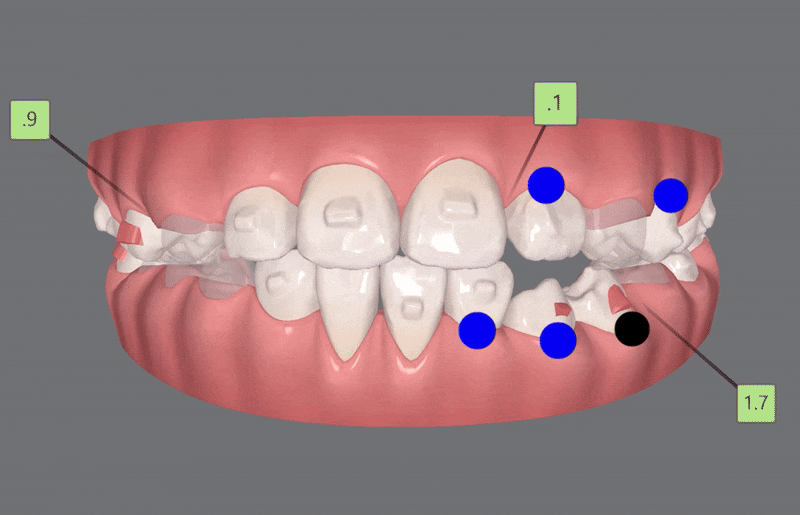

3rd(17개)

세번째는 17개의 장치로

이전의 클린체크를 이전의 클린체크를

상호 보완, 개선 하여 마무리 해드렸습니다.

4th (22개)

마지막으로 섬세한 디테일링을 위해

네번째 클린체크

(총 22개의 장치)를 진행해드렸습니다.

인비절라인퍼스트로 1차, 2차교정까지 마무리된 사진입니다 :)

치열이 고르지 않고

반대교합으로 아래턱이 도드라져 보였던 이전과 달리

청소년기인비절라인 교정 후

반대교합이 개선되고

맹출되지 않았던 앞니의 공간이 생기며

치아들이 제 위치를 찾고

정중선이 맞아지고 치열이 가지런해지면서

보다 자연스러운 미소를 지어주었습니다 :)